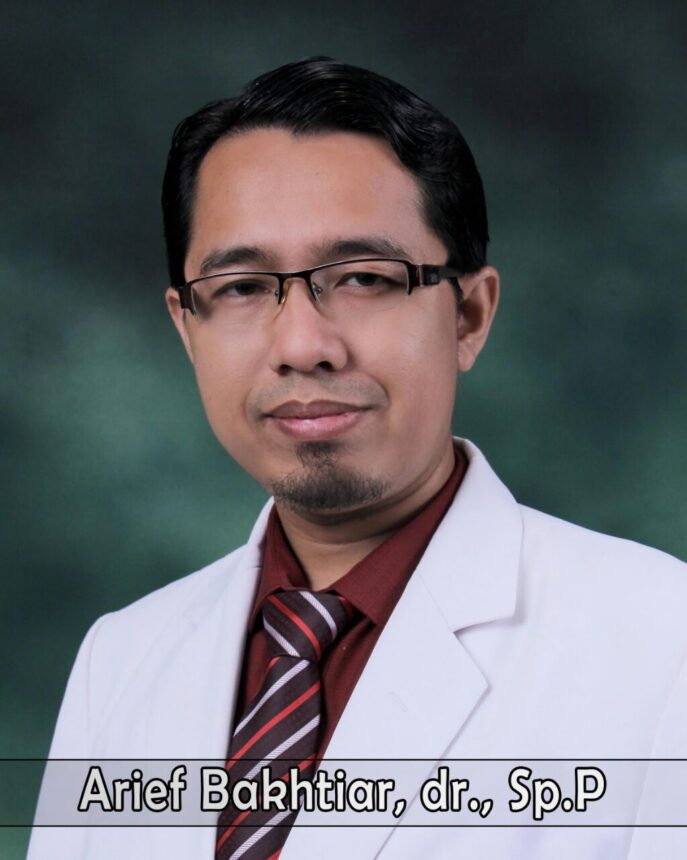

Menurut Ketua Persatuan Dokter Paru Indonesia, Jawa Timur, dr. Arief Bachtiar, Sp.P masih ditemukan pasien wanita merupakan tanda kanker ini bisa menyerang siapa saja.

“Kanker paru memang umumnya lebih banyak dijumpai pada penderita pria karena jumlah perokok pria lebih banyak. Namun bukan berarti tidak ditemukan kanker paru pada wanita. Di RSUD Dr Soetomo masih ditemui kasus kanker paru pada wanita,” ungkap dr. Arief.

Dikatakan bahwa faktor risiko kanker paru adalah pajanan senyawa asbes, rokok dan polusi udara. “Pajanan senyawa asbes dalam jangka panjang memang menjadi salah satu faktor risiko timbulnya kanker paru dan kanker pada selaput pleura,yakni Mesothelioma,” tambahnya.

Oleh karena itu, ungkapnya, pemakaian asbes sudah dilarang di banyak negara. Sedangkan perokok pasif tetap berpotensi memicu kanker paru lebih besar daripada non perokok, namun masih lebih kecil dibandingkan perokok aktif. “Salah satu faktor risiko utama kanker paru yang bisa kita cegah adalah hindari pajanan rokok,” ungkap dr Arief. (ndi)